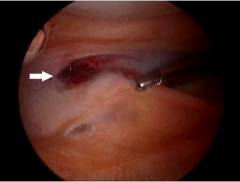

Артроскопия плечевого сустава: ход операции

- Осуществляют пункцию плечевого сустава: в него вводят иглу от шприца и подают через нее физиологический раствор. Это нужно для того, чтобы полость сустава растянулась, и в нее можно было ввести артроскоп, не повредив хрящи.

- Затем делают надрез на коже, и суставную полость прокалывают троакаром. Вводят артроскоп и осуществляют осмотр. Через артроскоп в полость сустава подают физиологический раствор для промывания и улучшения видимости.

- При необходимости делают дополнительные проколы и вводят через них хирургические инструменты.